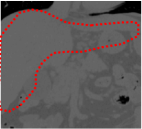

An example of CT/CBCT and MR/CBCT registration results are shown in figures 3 and 4, respectively. For both cases, the CBCT image (first column) was acquired intra-operatively after needle insertions and was employed as a reference for image registration. The pre-operative image is displayed before registration (second column), after PM-EA (third column) and after PM-EA+Evo (fourth column). The occurrence of patch shifts is reported for each spatial direction in panels (m–o): for each histogram, the shift with maximal occurrence is shown by the red dashed line. For panels (a–l), a ROI — manually defined on the CBCT image/encompassing the liver — is shown using red dash lines. Our visualization shows an improved correspondence of the contour of the liver with the manually defined liver boundary when the PM-EA solution is employed (see 3(c,g,k) and 4(c,g,k)). Moreover, an even better correspondence of the contour is observable using the PM-EA+Evo solution (see 3(d,h,l) and 4(d,h,l)).

Trans.

[X-Y]

CBCT

(a)

MRI / No registration

(b)

MRI / PM-EA

(c)

MRI / PM-EA+Evo

(d)

Sag.

[X-Z]

(e)

(f)

(g)

(h)

Cor.

[Y-Z]

(i)

(j)

(k)

(l)

(m)

(n)

(o)